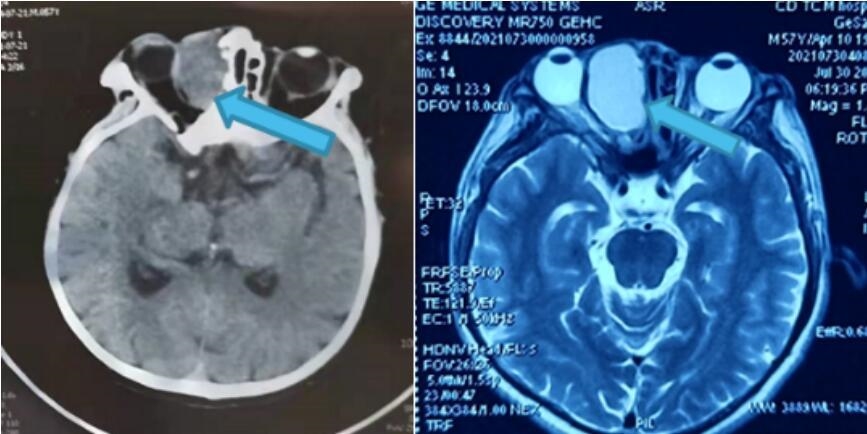

7月31日,格大哥来到成都爱尔眼科医院就诊,经过CT及MRI检查影像显示,眼眶肿物与筛窦相通,局部骨质缺损,眼球受压变形,如不及时治疗,将严重影响他的右眼功能。

由于眼眶解剖结构复杂,且和颅脑接近,肿瘤常常和神经、血管粘连非常紧密,不同性质的肿瘤有不同的手术治疗方案,治疗难度较高。为稳妥起见,接诊的黄山川医生及时发起由享受国务院特殊津贴专家孙丰源教授领衔的四川眼科医院、成都爱尔眼科医院、成都东区爱尔眼科医院三院眼眶病团队线上会诊,对患者的临床表现及影像学检查结果进行分析,迅速制定手术方案及手术风险预判。